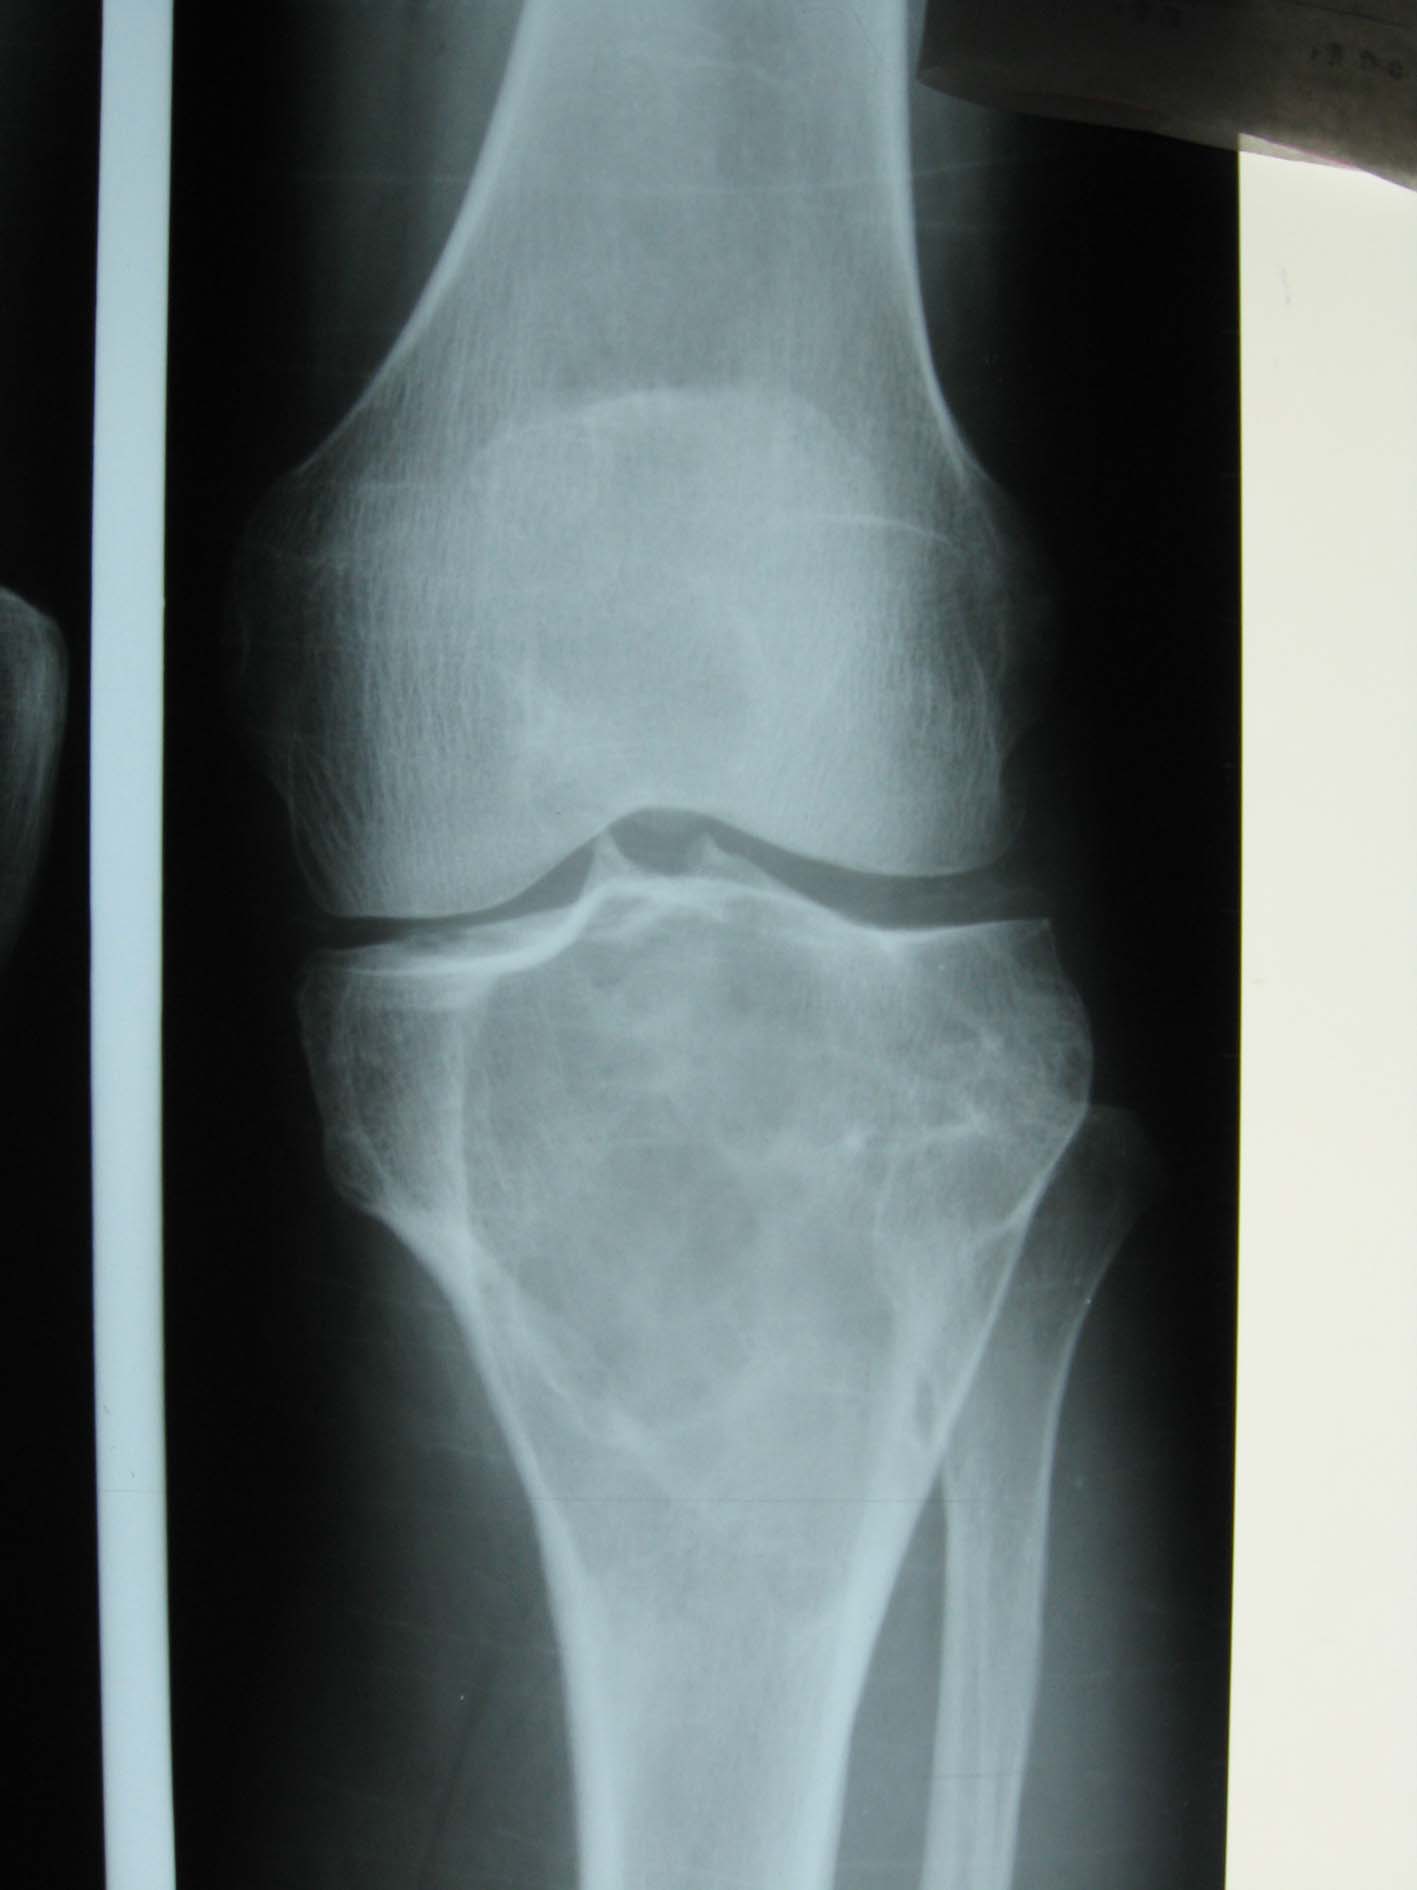

以下是引用流星1234在2009-3-9 22:19:00的发言:[br]胫骨骨端巨大囊性膨胀性溶骨破坏,与正常骨分界清楚,无硬化缘,其内有纤细间隔,呈皂泡状改变,支持骨巨细胞瘤.

以下是引用黑白光影在2009-3-9 22:59:00的发言:[br]本例患者膝关节可见胫骨髁间棘骨质增生变尖,髌骨后上缘亦有轻度增生改变,应为成年人。考虑胫骨上端骨巨细胞瘤可能性大。[br][br]骨巨细胞瘤:发病年龄较大,病变多位于长骨端有关节面下方,关节面常为肿瘤的部分轮廓。。由于肿瘤的纵行横行生长差不多,故肿瘤多呈球形。瘤内有皂泡状影。骨化及反应性骨硬化现象少见。而动脉瘤样骨囊肿发病年龄较轻,病变多位于干骺端,很少侵犯骨骺,常有不同程度的骨硬化现象。[br][br]鉴别诊断:[br]1、孤立性骨囊肿,多见于四肢,常为中心型,呈对称性轻度膨胀的骨破坏,周围为致密硬化带。囊壁外缘光滑整 齐,内缘则不光整。随骨骼生长逐渐移向骨干,常因病理性骨折而发现。[br]2、非骨化纤维瘤,常侵犯骨皮质,沿骨干蔓延,呈分叶状,边缘有硬化现象。有时边缘不完整,甚至有骨皮质断裂。[br]3、软骨粘液样纤维瘤,多见于青少年,偏心生长,分叶状,并呈分房样。突入软组织时多无包壳。破坏区内有斑点及斑片状钙化。[br]4、还有骨血管瘤、良性骨母细胞瘤,骨嗜酸性肉芽肿。[br][br][本贴已被 黑白光影 于 2009-3-9 23:00:25 修改过]